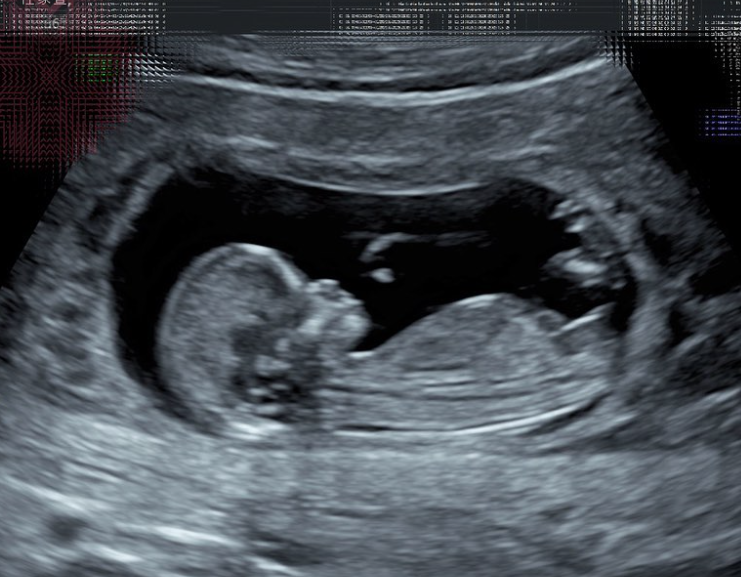

41歲的Selina任家萱於今日(13日)在微博宣布喜訊,稱自己已經懷孕12周,晉級成為媽媽,同時公布BB小名「小腰果」。Selina指,這個突如其來的小生命讓她感到不可思議,更曬出超聲波照片和媽媽手冊照,配文寫道:「春暖花開,我的腰果也來了!」

Selina自去年3月認愛小7歲的圈外男友後,不時在社交媒體曬出恩愛的甜蜜照片。她今日更宣布喜訊,指目前已懷孕12周,晉級成為媽媽,BB小名取為「小腰果」。Selina還透露其實早在第2周就聽到「小腰果」的心跳,當下讓兩人非常激動。而Selina為了向大家宣布這個幸福的瞬間,更曬出了超音波照片與父母的育兒手冊。在超音波的照片中,可以隱約看見小腰果的雙腿,中間還有一條粗粗的條狀物體,Selina笑稱「很大條」,甚至一度以為是男生,結果醫生解釋那只是「臍帶」。